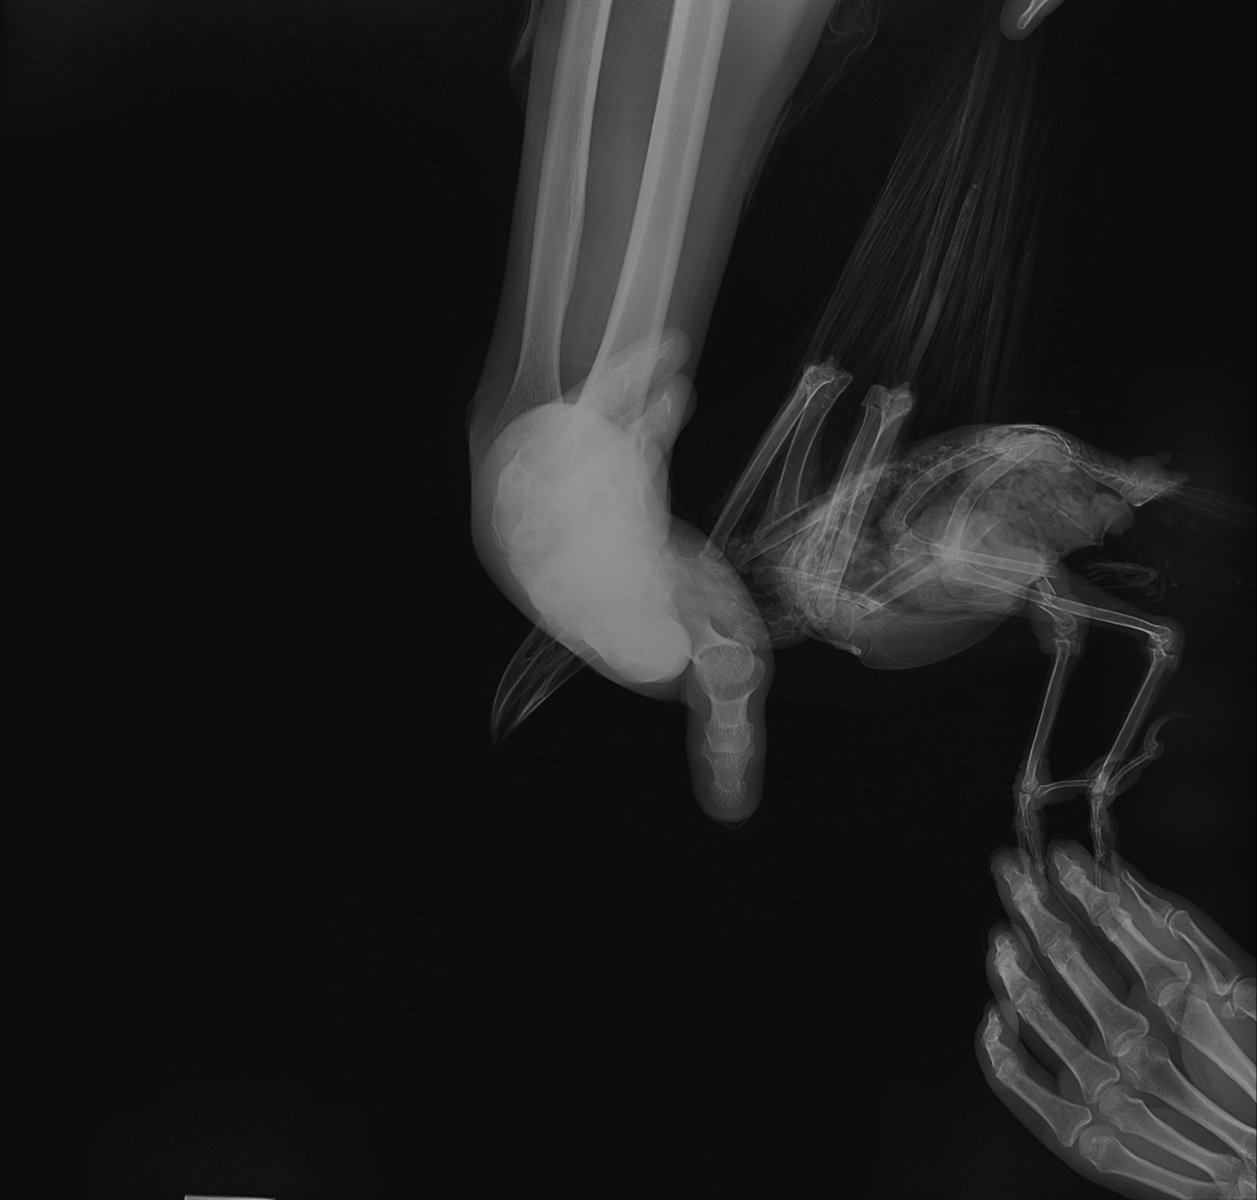

2. Перелом открытый, как выглядит (фото)?

20240905005_Дегтянникова_Ворона_20240905162112.jpeg

20240905005_Дегтянникова_Ворона_20240905162124.jpeg

20240905005_Дегтянникова_Ворона_20240905162136.jpeg

У меня остаются подозрения, что где-то есть открытая рана, личинки не могут быть просто так. По рентгену не вижу, где могла бы быть. Лучше обратиться к Zosia, чтобы посмотрела рентген, быстрее будет по Вацапу в ее профиле.